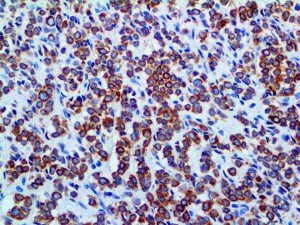

It is the ICU physician who is most likely to witness one of the deadliest manifestations of the abnormal immunological response, the cytokine storm syndrome (CSS). This response is also referred to by some as the cytokine release syndrome (CRS). CSS is characterized by continuous activation and expansion of macrophage and lymphocyte populations, which secrete large amounts of cytokines, causing the cytokine storm. This massive cytokine release is akin to hemophagocytic lymphohistiocytosis (HLH) disease, a syndrome characterized by initial unchecked and persistent activation of cytotoxic T lymphocytes and NK cells.